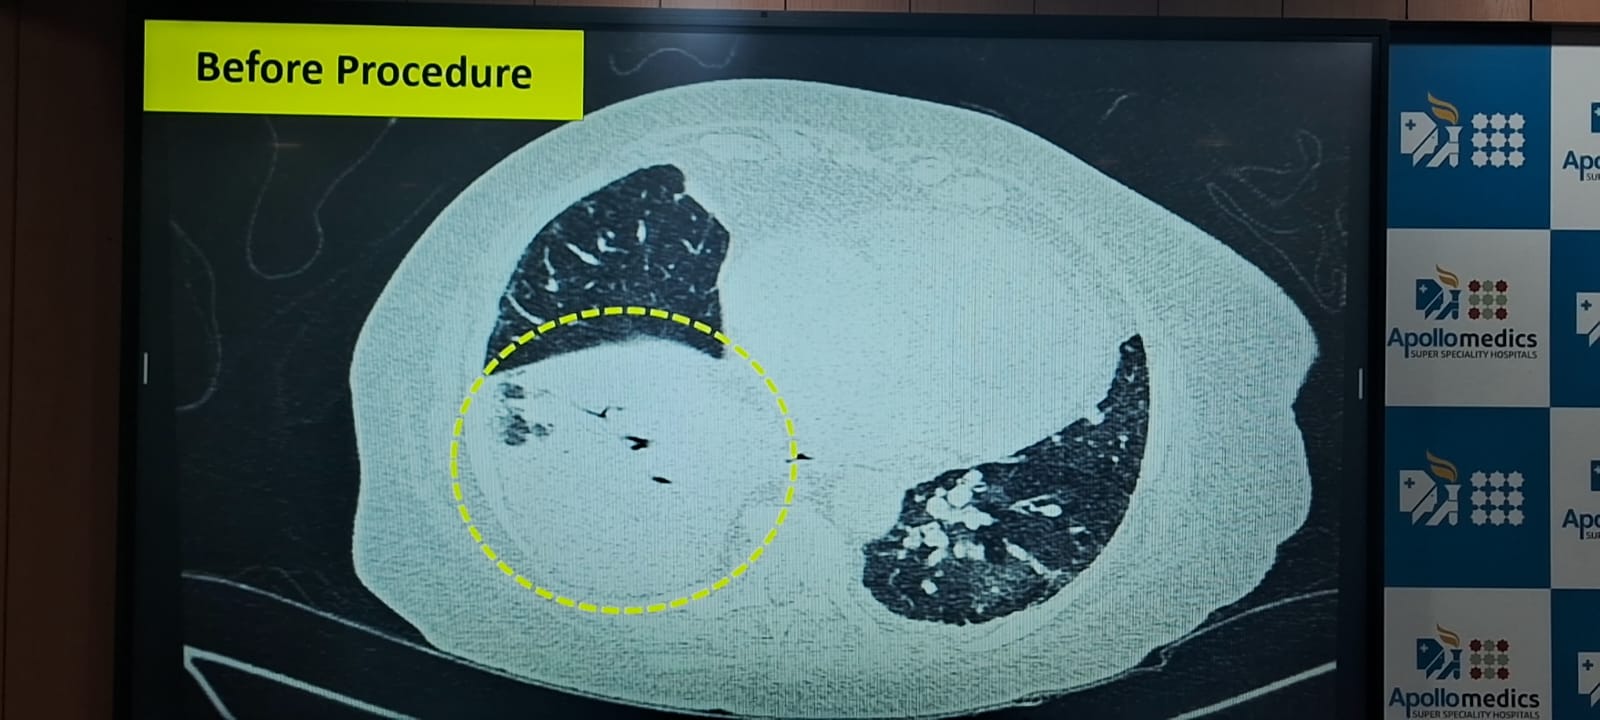

हाल ही में अपोलो हॉस्पिटल में कुछ ऐसा ही केस देखने को मिला। जहां करीब 70 साल की एक बुजुर्ग महिला बार-बार छाती में संक्रमण और निमोनिया की शिकायत के साथ अस्पताल में आई। हालत ज्यादा खराब होने की वजह से उसे आईसीयू में भर्ती कराना पड़ा। इस दौरान एक्स-रे और सीटी स्कैन की जांच में उनके फेफड़ों में निमोनिया पाया गया। मरीज को पहले से हृदय संबंधी समस्या, हाई ब्लड प्रेशर था और वह ब्लड थिनर भी ले रही थी। बीमारी के कारण को समझने के लिए डॉक्टरों ने ब्रोंकोस्कोपी करने का निर्णय लिया।

अपोलो हॉस्पिटल के पल्मोनोलॉजिस्ट डॉ. शुभम अग्रवाल ने बताया कि ब्रोंकोस्कोपी के दौरान यह देखा गया कि जिस हिस्से में निमोनिया था, वहां फेफड़े के अंदर कोई वस्तु फंसी हुई है। डॉक्टरों ने परिजनों को बताया कि उस वस्तु को निकालना बेहद जरूरी है और इसके लिए जनरल एनेस्थीसिया और वेंटिलेटर की जरूरत पड़ेगी। प्रक्रिया लंबी होने के कारण परिवार पहले घबरा गया लेकिन बातचीत और समझाने के बाद उन्होंने सहमति दी।

इसके बाद मरीज को पूरी तरह बेहोश कर फेफड़ों के अंदर कैमरे और विशेष उपकरण की मदद से वह वस्तु बाहर निकाली गई। प्रक्रिया के दौरान हल्की ब्लीडिंग हुई, जिसे दवाओं से नियंत्रित कर लिया गया। जब वह वस्तु बाहर निकाली गई, तो वह सुपारी का एक टुकड़ा था। परिवार ने बताया कि मरीज को सुपारी चबाने की आदत थी और वह कई बार रात में भी मुंह में सुपारी रखकर सो जाती थीं। यही सुपारी का टुकड़ा उनके फेफड़ों में फंसा हुआ था और उसी की वजह से उन्हें लंबे समय से बार-बार संक्रमण हो रहा था। सुपारी का टुकड़ा निकालने के बाद मरीज की हालत तेजी से सुधरी, उन्हें वेंटिलेटर से हटा दिया गया और कुछ ही समय में वह स्वस्थ होकर घर लौट गई।